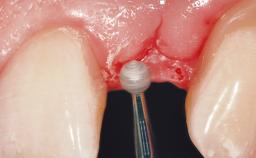

Immediate Placement of an Implant in a Maxillary Left Central Incisor Site

A 33-year-old female patient presented with an upper left central incisor that required extraction after a failed endodontic therapy. The tooth had been traumatized when the patient was a teenager and had undergone several endodontic treatments, including two apicectomy procedures. The patient was in good health and did not smoke. Clinical examination showed that the patient had a high lip line. In full smile, the gingival margins of the upper teeth were visible to the first molars. The gingival margins of central incisors 11 and 21 were only just showing. Examination of tooth 21 confirmed that the tooth was mobile and had hypererupted by 1 mm.